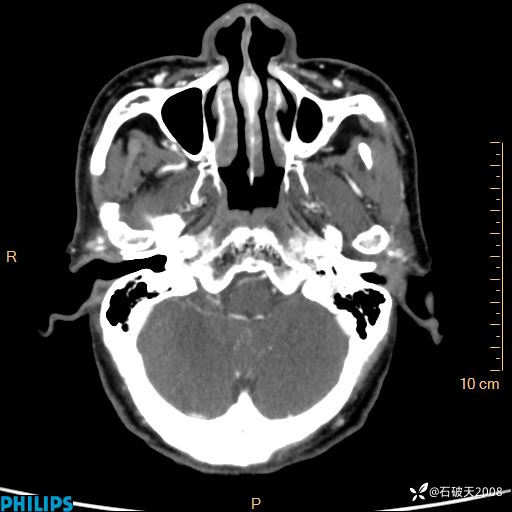

冠状位